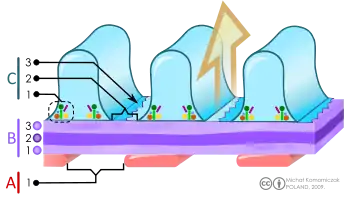

Scheme of filtration barrier (blood-urine) in the kidney. A. The endothelial cells of the glomerulus; 1. pore (fenestra). B. Glomerular basement membrane: 1. lamina rara interna 2. lamina densa 3. lamina rara externa C. Podocytes: 1. enzymatic and structural protein 2. filtration slit 3. diaphragm | |

The glomerular basement membrane contains three layers:[4]

| Layer | Location | Composition | Function |

| lamina rara externa | adjacent to podocyte processes | heparan sulfate

Sialoglycoproteins proteoglycans |

Heparan sulfate restricts movement of anionic particles.

Sialoglycoproteins glue cells on the GBM. |

| lamina densa | dark central zone | type 4 collagen and laminin | blocks by size (Molecular Weight > 70kDa) |

| lamina rara interna | adjacent to endothelial cells | heparan sulfate

Chondroitin sulphate |

blocks by charge |

The glomerular membrane consists of mesangial cells, modified pericytes that in other parts of the body separate capillaries from each other. The podocytes adjoining them have filtration slits of diameter 25 nm that are formed by the pseudopodia arising from them. The filtration slits are covered by a diaphragm that includes the transmembrane protein nephrin.